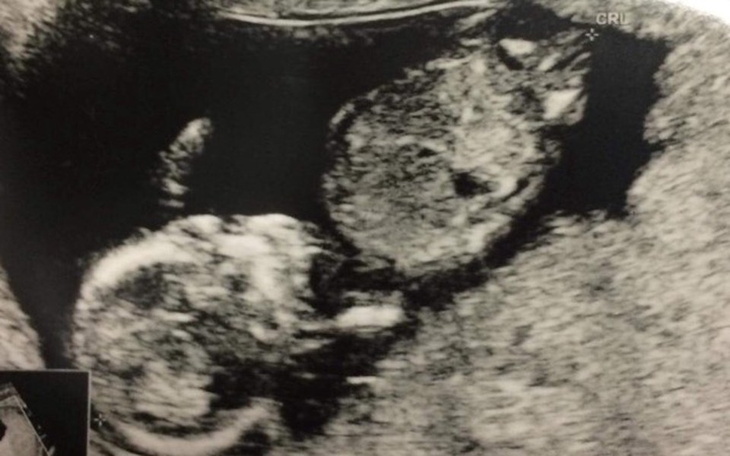

Leona jeszcze ze mną nie ma. Siedzi sobie grzecznie w brzuszku i czeka na swoją kolej:) Jak przystało na chłopca- rozrabia, kopie i łobuzuje:) Nie mogę się już doczekać, aż syn będzie ze mną. Chwila jego przyjścia na świat niesie za sobą jednak pewne „niespodzianki” do których chciałabym się odpowiednio wcześniej przygotować.

U Leona została wykryta ARSA czyli błądząca tętnica podobojczykowa. Dzieci z taką wadą bardzo często rodzą się z zespołem Downa. Istnieje sposób aby dowiedzieć się wcześniej czy dziecko będzie chore czy nie- Amniopunkcja. Koszt 1500zl. Możliwość wcześniejszego przygotowania się, wybranie odpowiedniej placówki do porodu oraz dalszej opieki to tylko kilka z korzyści jakie da mi to badanie.